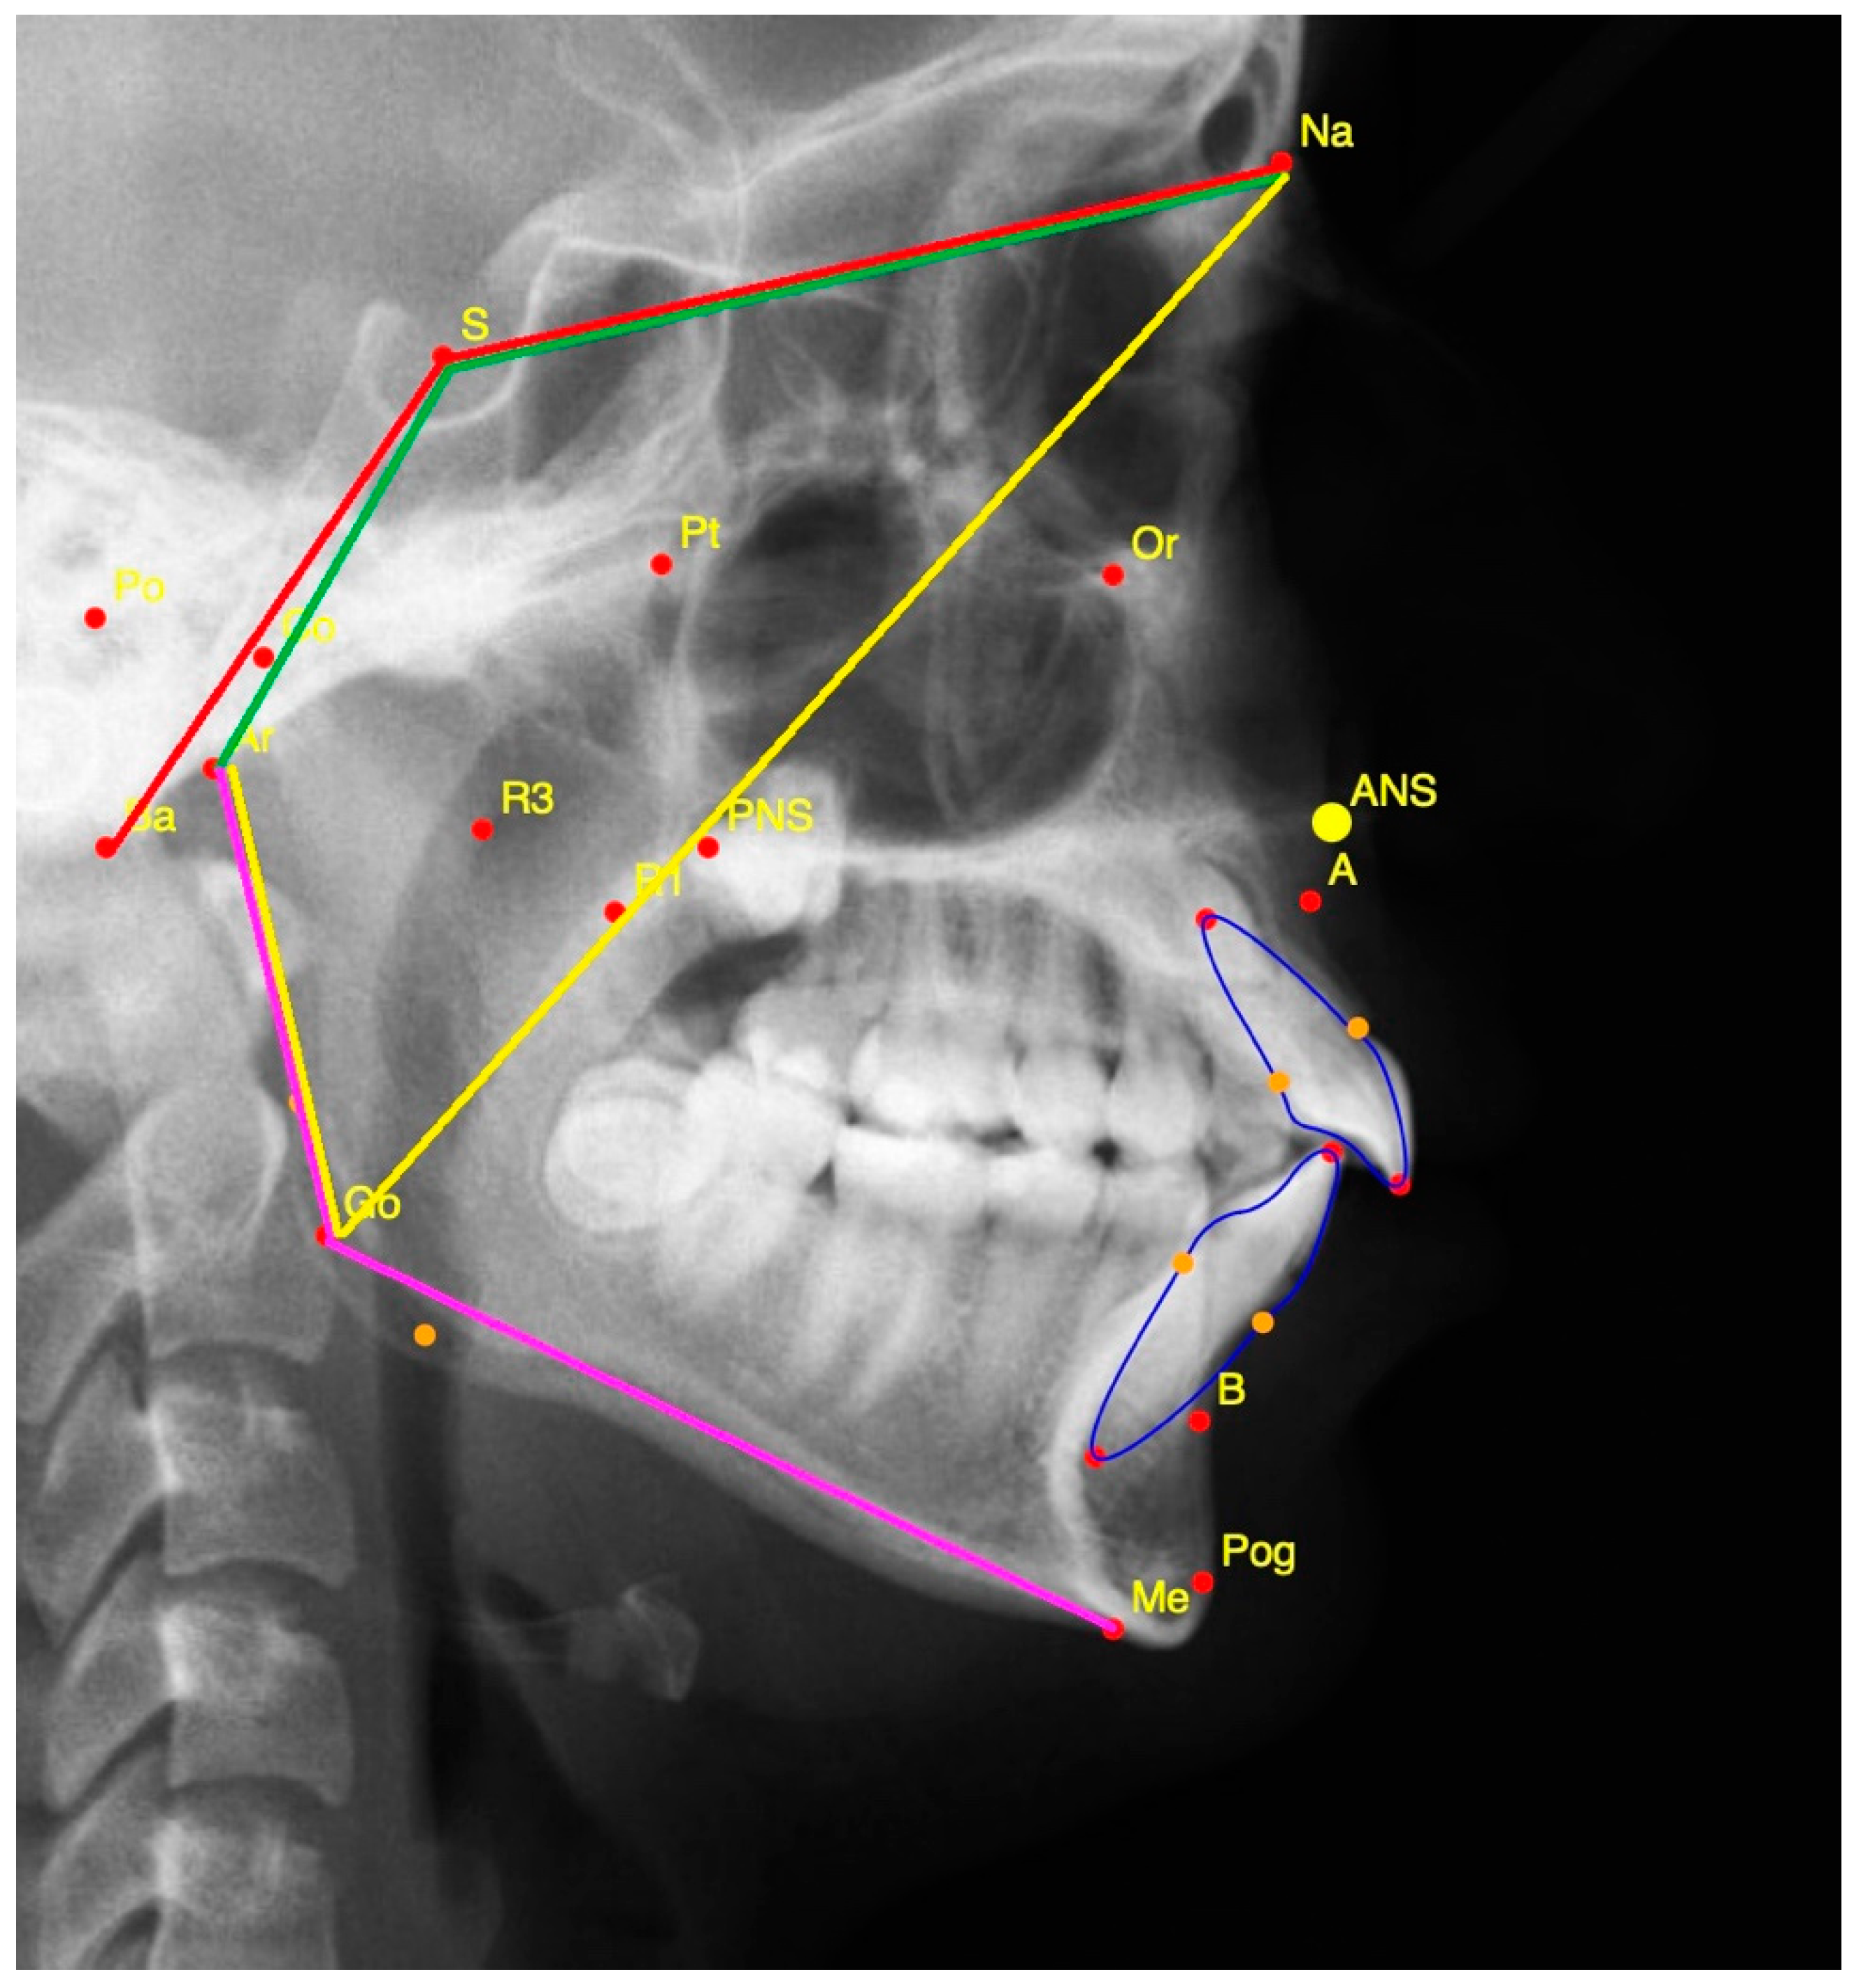

2.3. Measurements